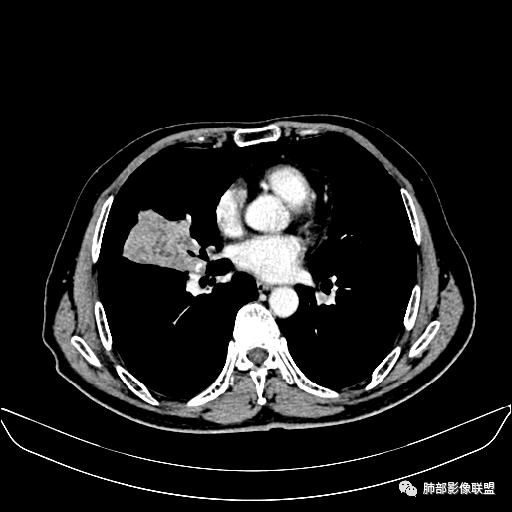

住院4天后行胸部增强CT

动脉期

老年男性,因“咳嗽咳痰1月余。”入院。病程中咳嗽咳痰,咳黄白痰,间断咯少许鲜红色痰血。PPD阳性。胸CT:右肺中叶外侧段支气管管腔阻塞,大片实性病变,病灶边缘光滑,部分边缘膨隆,可见分叶,肺门及纵隔可见肿大淋巴结,并可见钙化。增强可见病灶明显强化,而且延迟强化明显,病灶内多发低密度区,内见血管影,血管变细、部分血管破坏。考虑恶性病变可能性大,鉴别慢性肉芽肿性病变。

胸CT:跨叶大肿块,主体在中叶,右中叶外侧段支气管阻塞,病灶部分边缘膨隆,可见分叶,部分边缘平直,肺门及纵隔可见肿大淋巴结。增强病灶不均匀强化,延迟强化明显,病灶内多发低密度区,内见血管飘浮,部分血管变细、模糊。考虑:恶性病变可能性大,大细胞?淋巴瘤?鉴别慢性肉芽肿性病变。

右肺中叶软组织肿块,外围向内生长,叶间胸膜向前内移位,肿块近肺门侧跨叶,中叶外侧段支气管截断,密度不均匀,双侧肺门及隆突下见肿大淋巴结,增强后呈中度不均质强化,肺动脉供血,多发坏死区,边界尚清,坏死区域内见结构,结合病史考虑恶性,鉴别诊断1结核,爬行征是沿支气管树分布,外宽,内窄,周围有卫星灶,内气管狭窄后扩张,此例沿叶间胸膜长轴分布,气管有截断,不典型。2炎性肉芽肿,符合的地方下方层面增强后延迟性轻度环形强化,不符临床无发热等急性感染病史,实验室指标不符,病灶周围渗出及慢性炎性改变有,不明显。